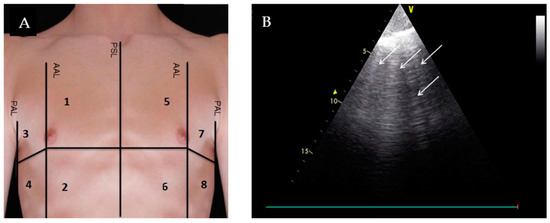

| Lung Ultrasound | ||||

| Evaluation for B-lines | Absence of B-lines |

|

| |